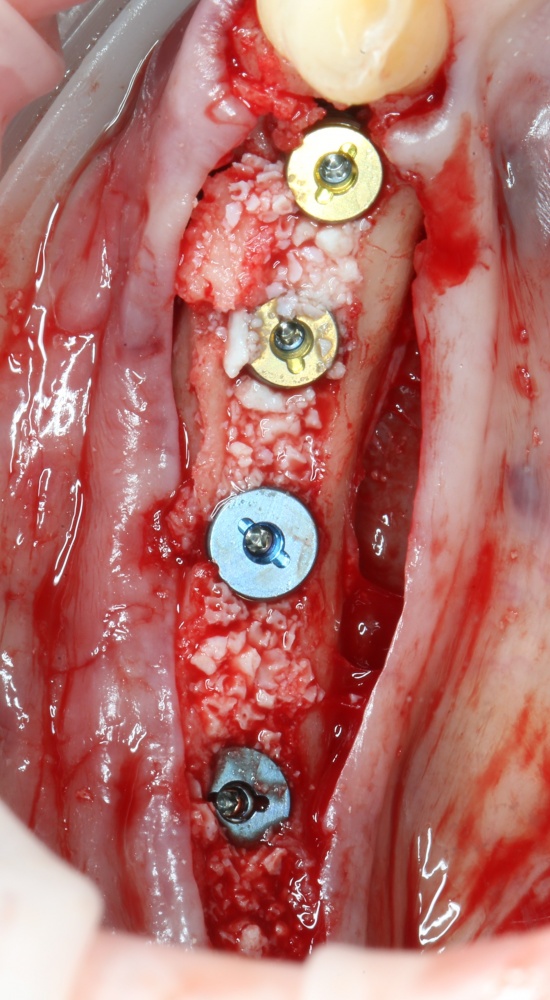

Использование металлоконструкций

Поэтому для реализации остеотомии нам нужны:

— винты. Разных размеров. Для фиксации пластин подойдут самые маленькие — 3-4 мм. Для фиксации самих костных фрагментов или «домкрата» потребуются винты длиннее — 10-12 мм.

— минипластины. Их выпускается огромное количество. Мы используем, в основном, X- и Н-образные минипластины наименьших размеров — с ними легче работать, они легко адаптируются, но есть и минус — иногда гнутся под нагрузкой.

Мы особо не паримся с металлом, предпочитая ритм-энд-блюз или джаз, но если приходится, то нас вполне устраивает отечественный производитель «Коррозия металла» КОНМЕТ:

Во-первых, недорого. Во-вторых, качество, я бы сказал, на уровне.

За редким исключением, минипластины и винты перед имплантацией нужно удалить.

При горизонтальной остеотомии, на мой взгляд, удобнее использовать минипластины. Как я уже отмечал выше, в практике мы используем X- и H-образные минипластины под винты размером 0.9х4мм. Количество металла в разных условиях может быть разным — всё зависит от того, на каком этапе достигается полная неподвижность перемещенного костного фрагмента.

7. Заполнение образовавшегося пространства графтом.

В какой момент это делать? Наверное, если Вы используете графт в виде твердого блока, то, мне кажется. разумнее сначала уложить графт, затем проводить фиксацию перемещенного костного фрагмента винтами или минипластинами: